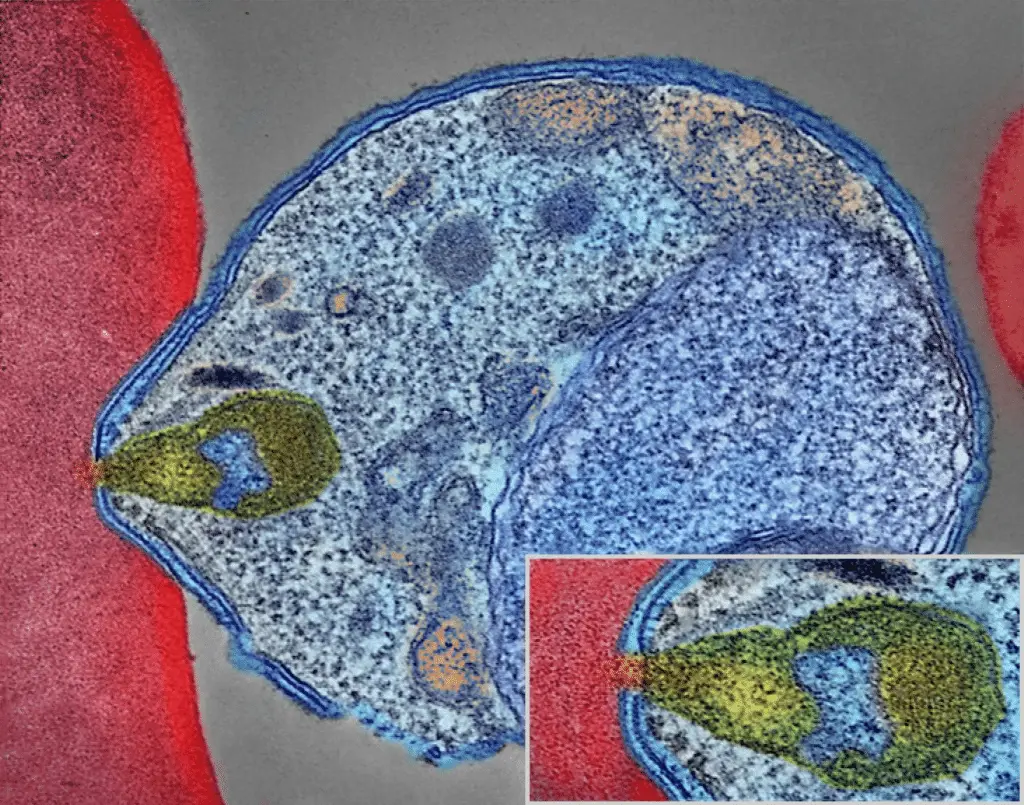

A differenza delle cellule umane, il parassita utilizza un meccanismo di divisione più complesso e meno “standard”. I ricercatori hanno scoperto che ARK1 svolge un ruolo centrale nell’organizzazione del fuso mitotico, la struttura che separa il materiale genetico consentendo la formazione di nuove cellule parassitarie.

Negli esperimenti di laboratorio, la disattivazione della proteina ha portato a un rapido collasso dello sviluppo del parassita. Senza ARK1, il Plasmodium non riesce a formare correttamente il fuso mitotico e quindi non può dividersi in modo efficace.